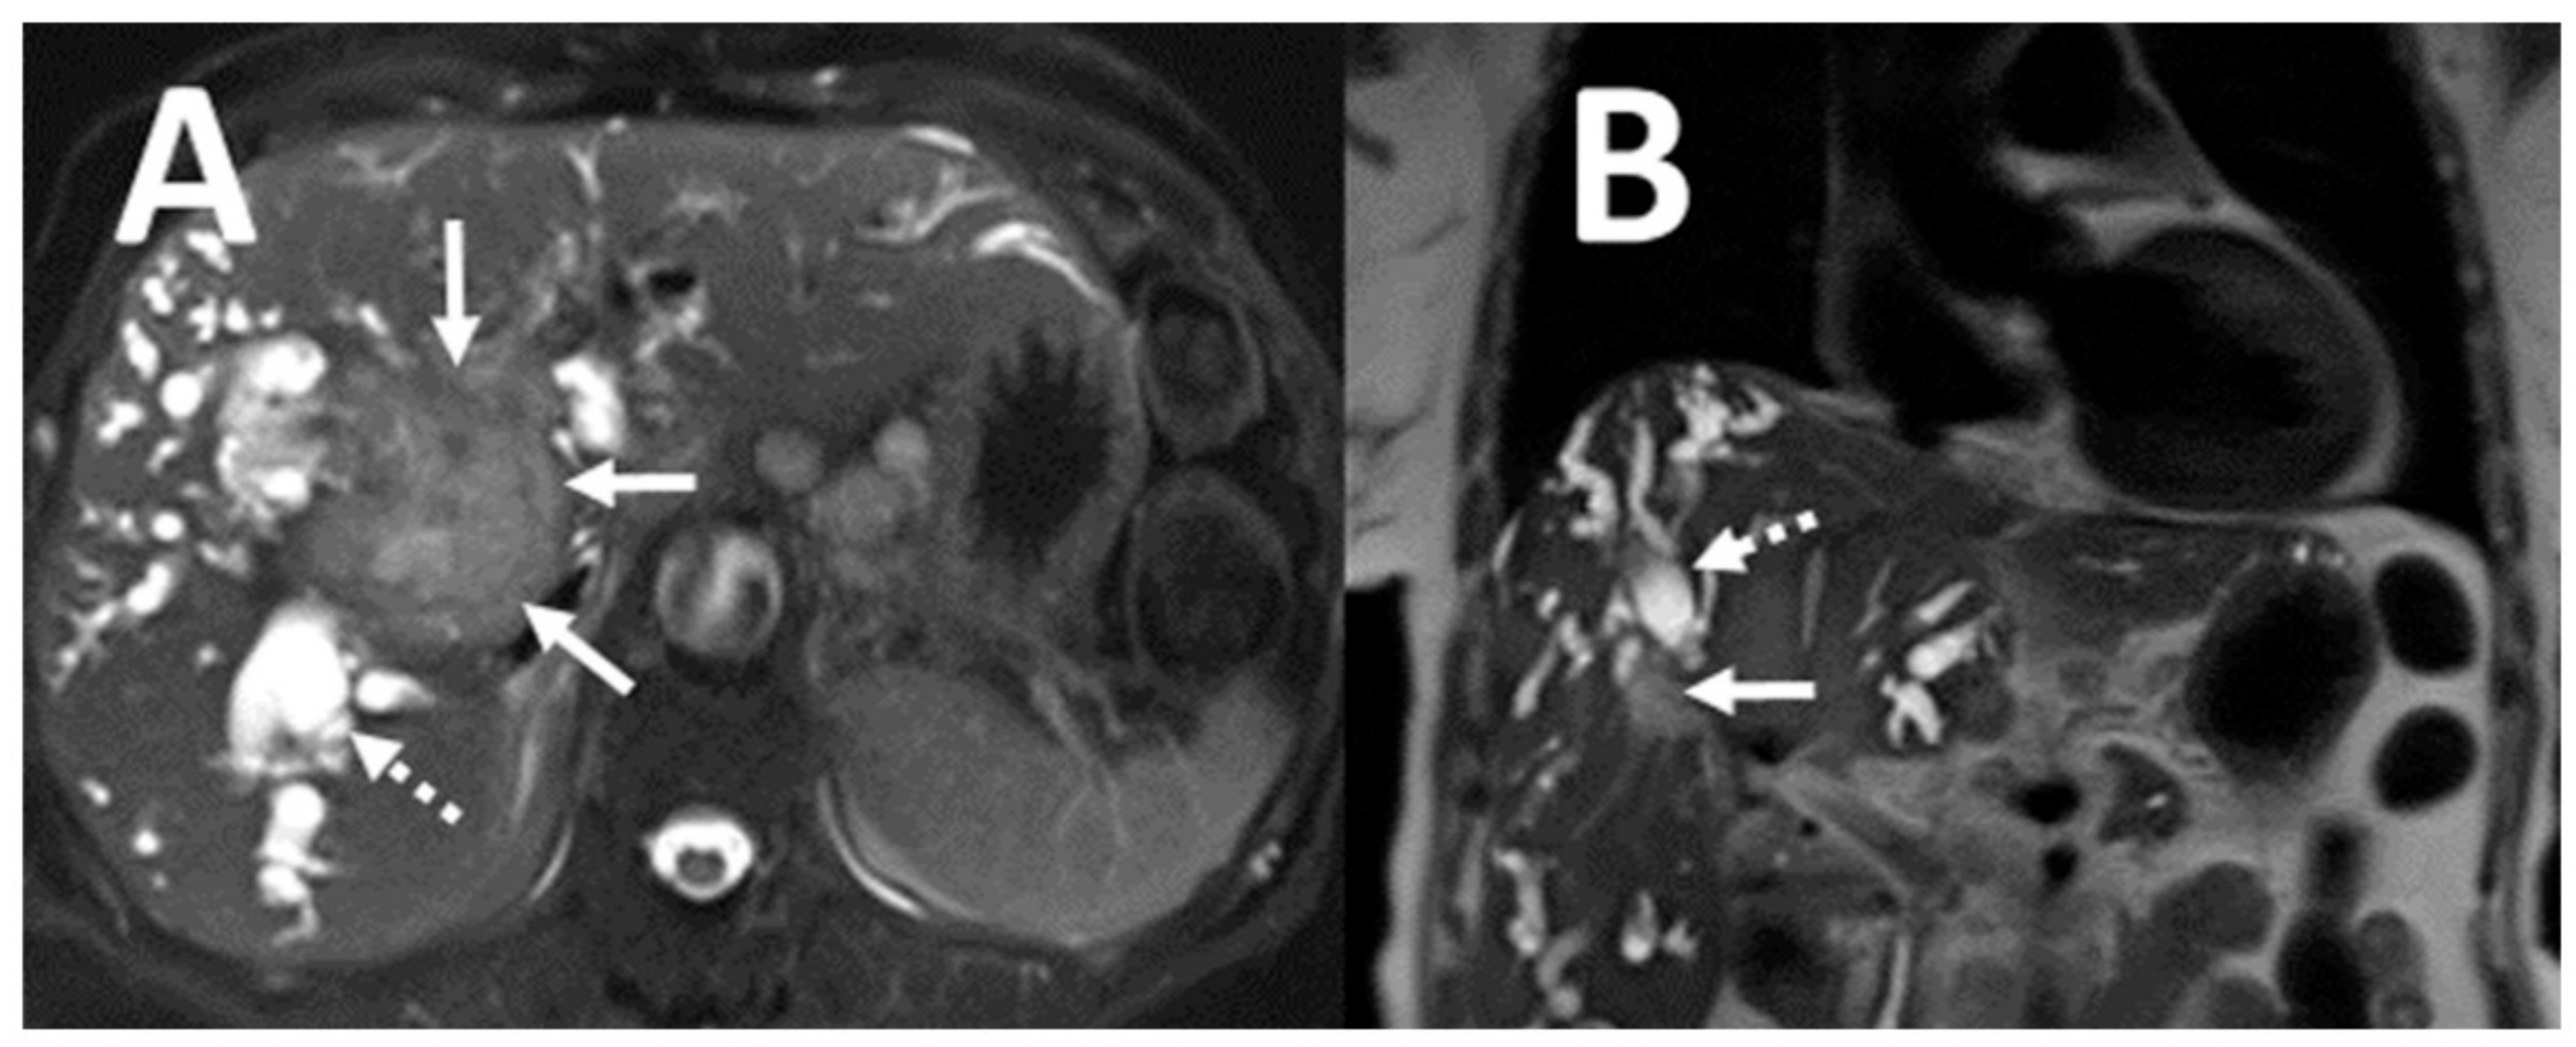

3. Results